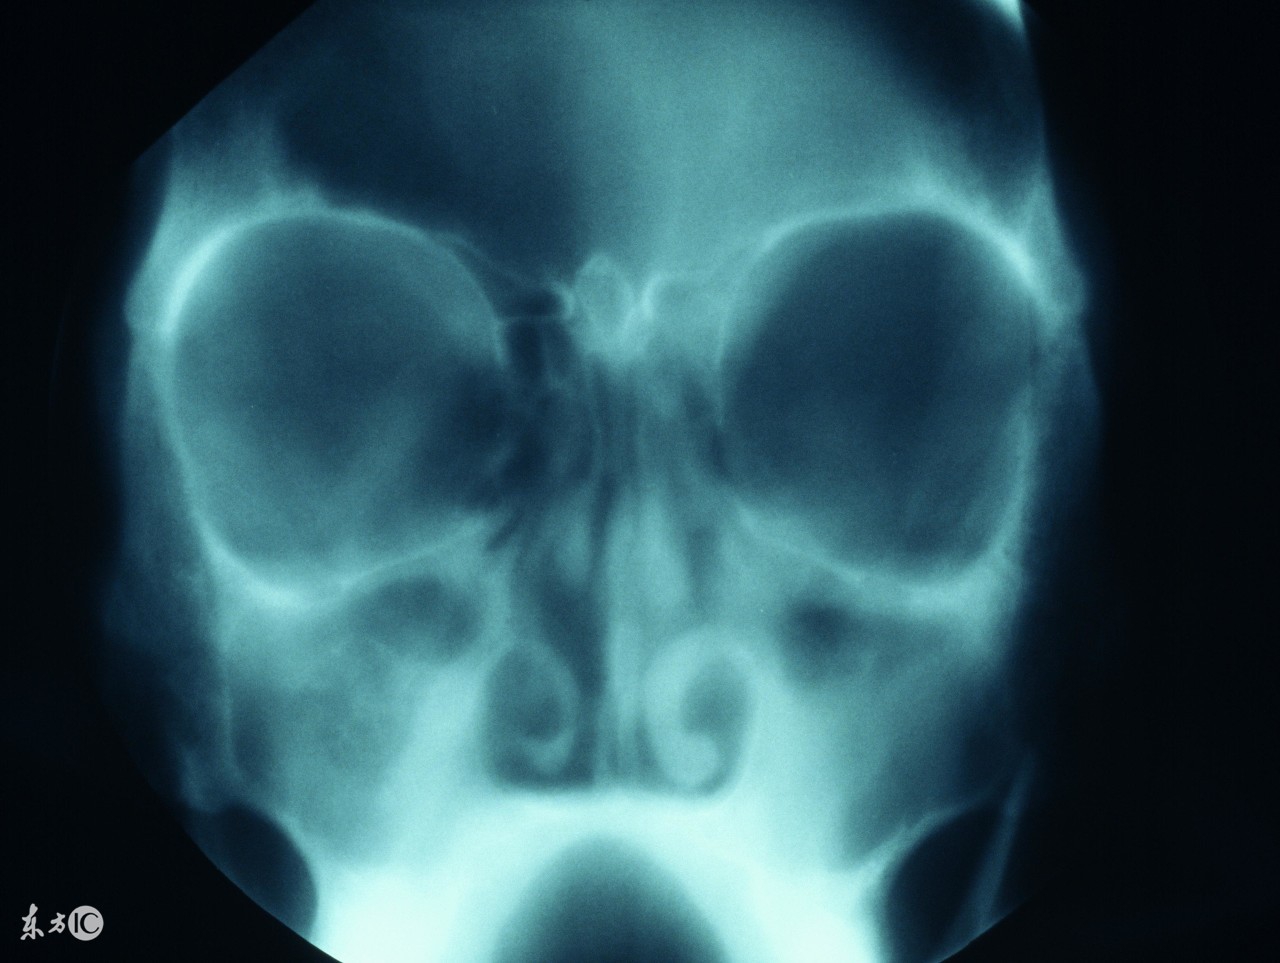

鼻窦炎其实是生活中比较常见的鼻科疾病,虽然很常见,但是其危害却也不可小看,今天就来讲讲鼻窦炎会带来的一连串的严重后果:

三、诱发颅内并发症;与分泌物向下引流对应的还有病灶上行引起的颅内并发症,严重的还会出现对侧面部和上肢肌肉瘫痪或者抽搐,肿泡溃疡破裂以及引起化脓性脑膜炎。